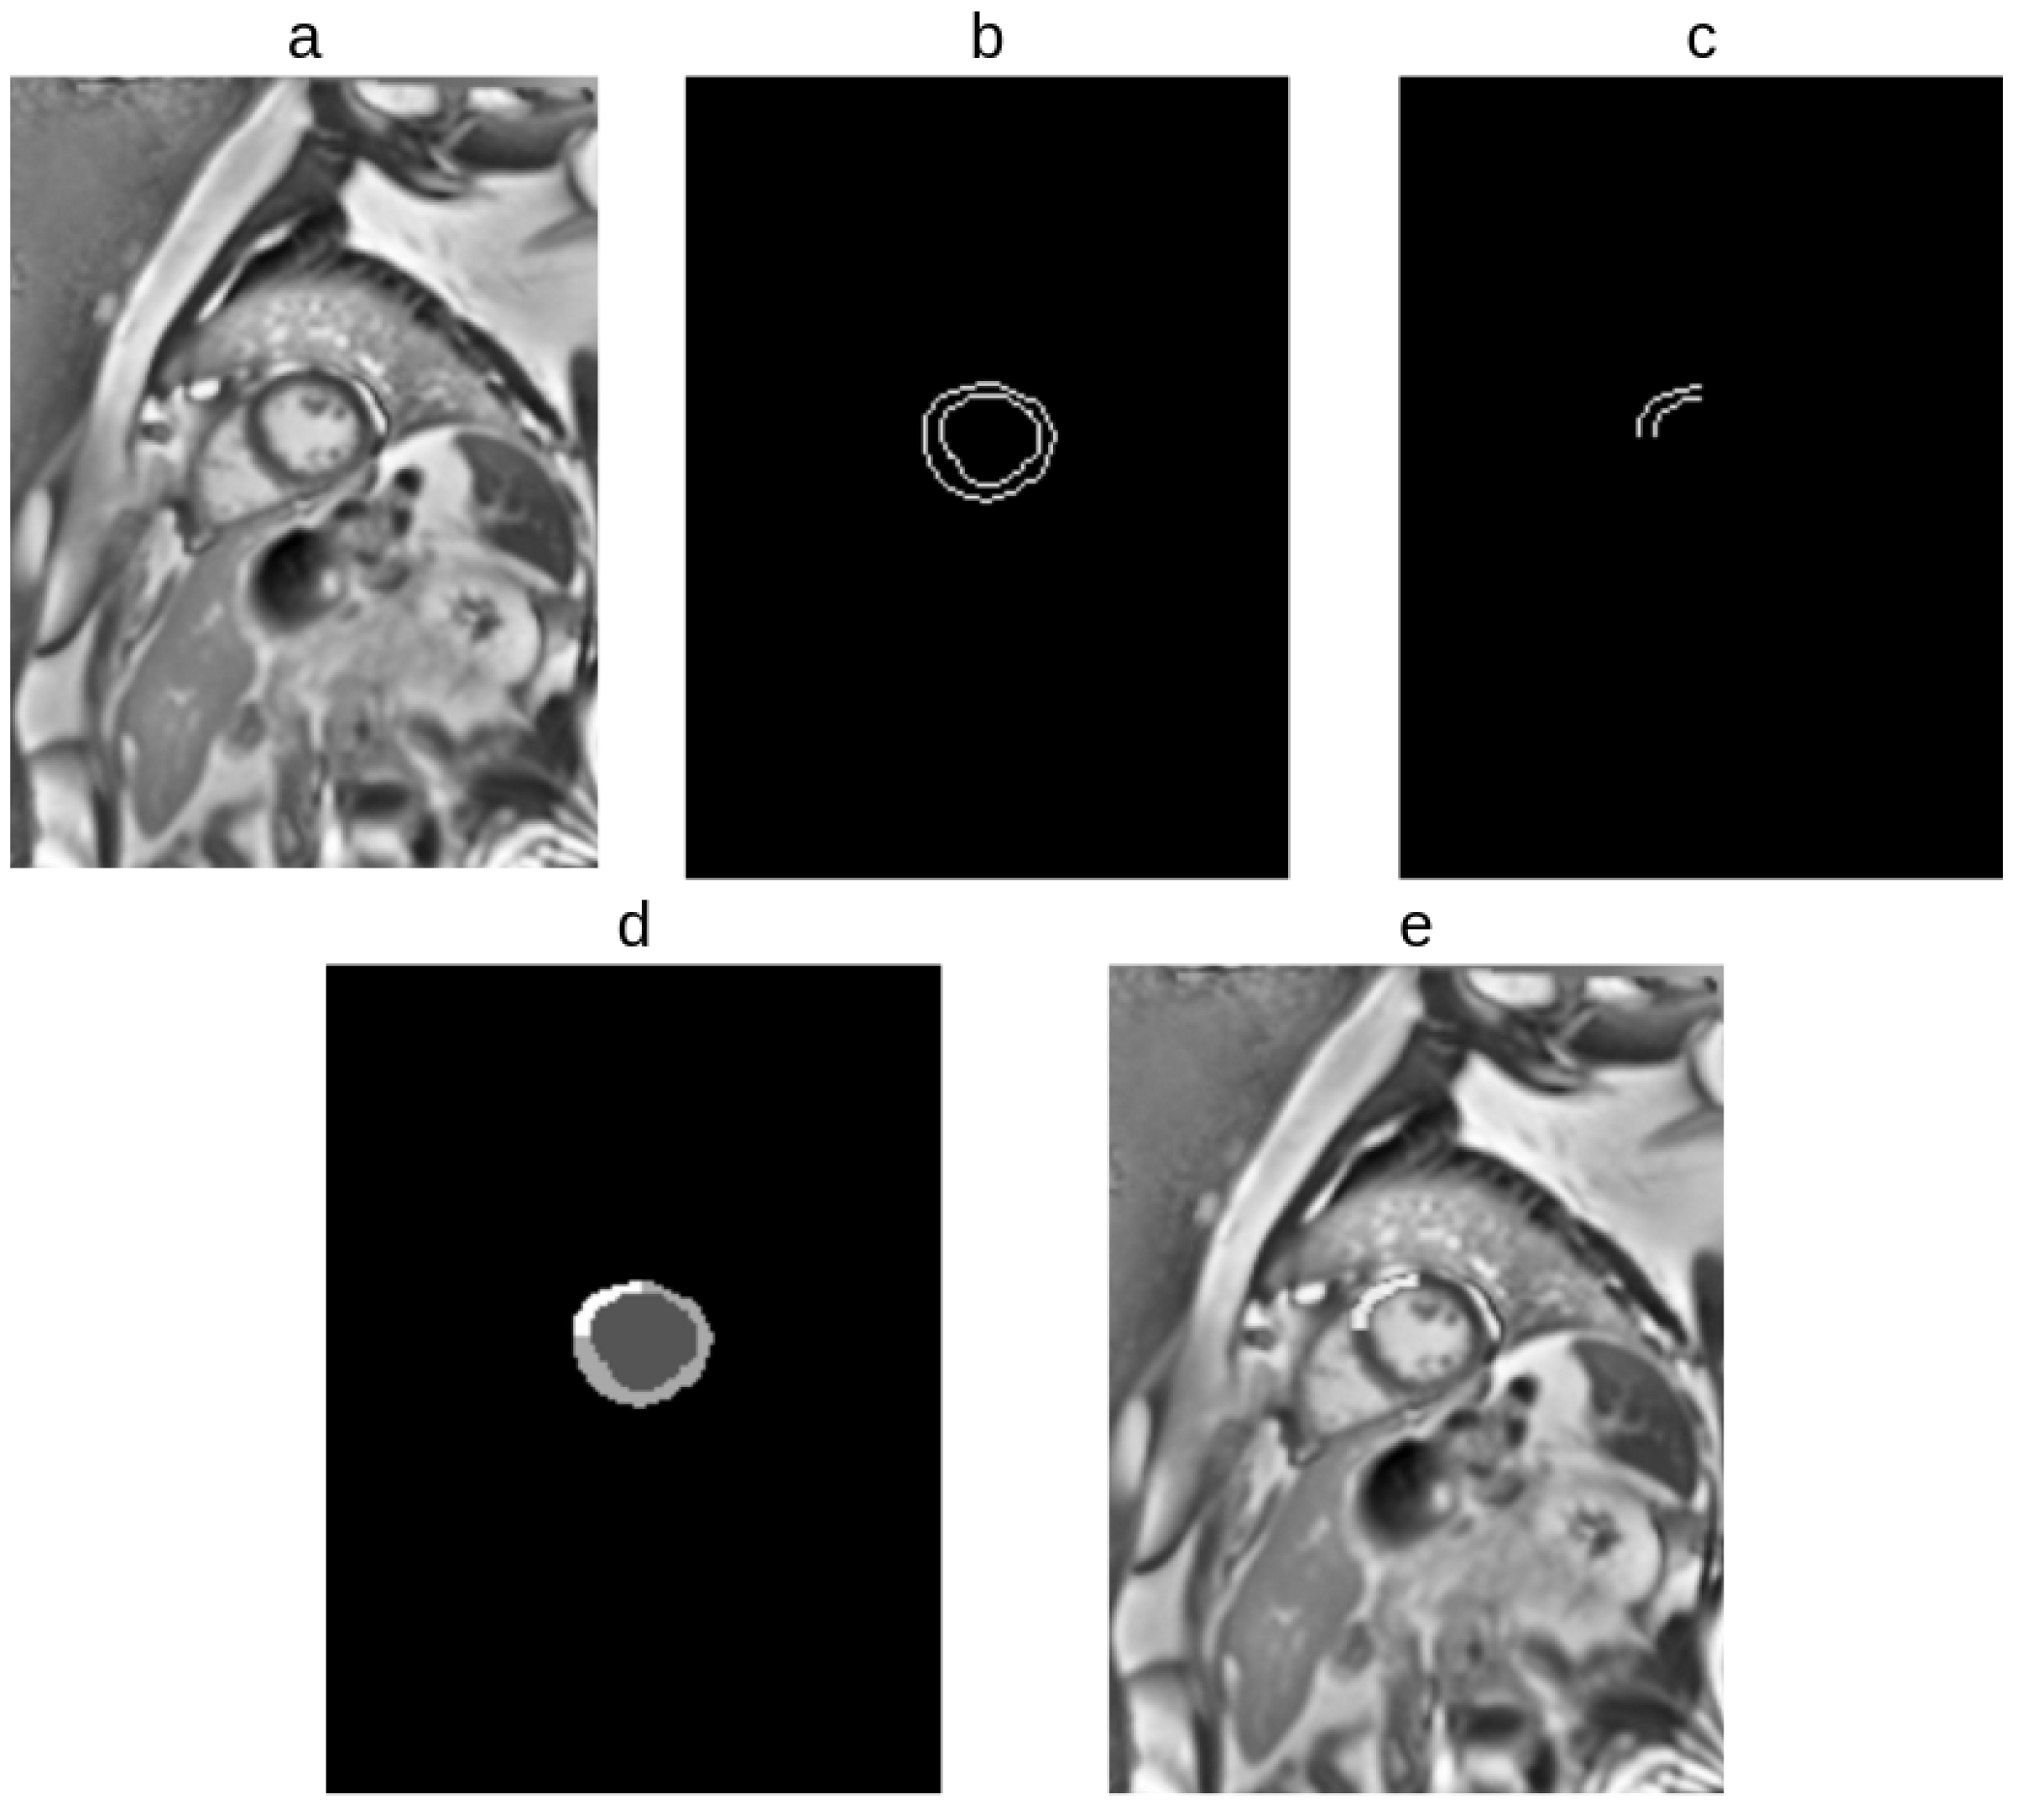

2.2.3. Extraction of Prior Information from EMIDEC Dataset

2.2.4. Data Augmentation Approach